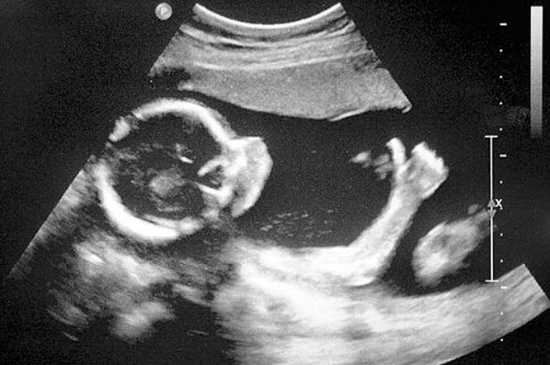

b.四肢